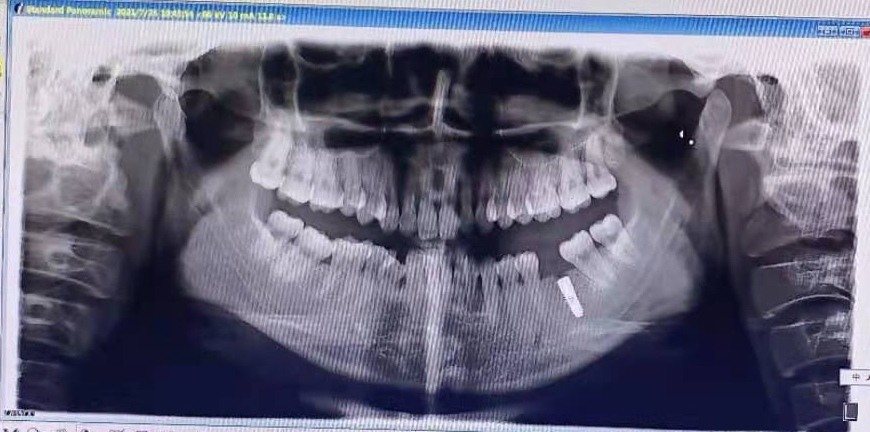

28岁的小然(化名),因左下大牙缺失到我院口腔门诊咨询就诊。经过口腔科张义仁医生的仔细检查,小然符合种植牙条件。通过对小然进行全身系统检查评估、口腔CBCT、模型分析等检查后,张医生为她进行种植体设计,并进行了术前沟通。手术中,医务人员严把无菌操作和手术流程关,让小然在无痛舒适的情况下顺利植入4×11mm种植体,整个过程安全、精准,为二期修复手术打下良好基础。

种植牙手术前后对比如图: